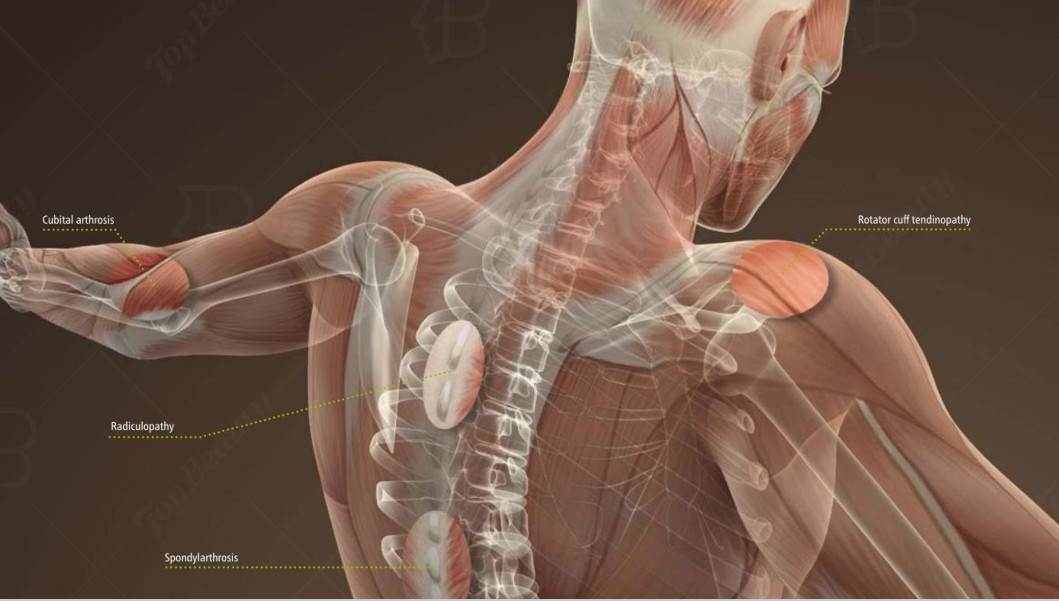

Feature : Degenerative joint diseases

Application : Pain treatment Chronic pain/Chronic inflammation of tendons and joints

Function : Pain treatment Chronic pain

Extracorporeal Magnetic Transduction Therapy EMTT Field Pain Relief PEMF Machine

Degenerative joint diseases Osteoarthritis (knees, hips, hands, shoulders, elbows)

Disorders of the active and passive musculoskeletal system are the most common cause of pain

(chronic or otherwise) around the globe. These disorders include back pain and osteoarthritis as well as

typical sports injuries such as inflammation of the tendons and joints. People who suffer from these

conditions often experience significant limitations in their everyday life as well as reduced quality of life.

Extracorporeal Magnetotransduction Therapy (EMTT) is a non-invasive procedure developed specifically

for the treatment of these conditions. It differs from other forms of magnetic field therapy in its higher

oscillation frequency and magnetic field strength, also known as effective transduction power. It is

believed that these properties can enhance the healing processes in the body.